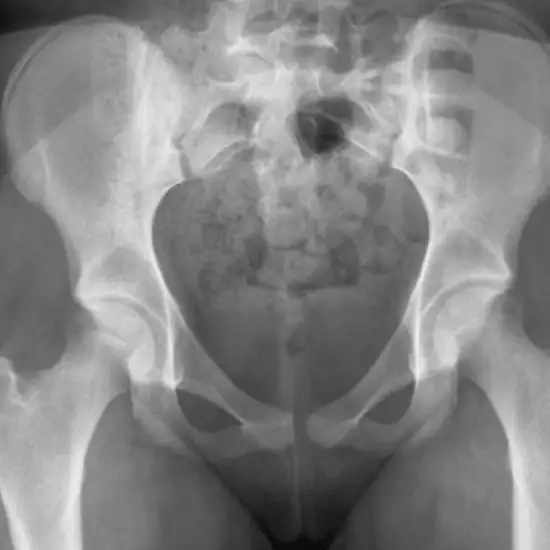

Both hip joints (AP View) x-ray test is used to visualize the pelvis, the hip joint's bones, and the soft tissues (skin and muscles) that enclose them.

When a doctor orders this test, it will be used to diagnose any hip fractures, track the healing of the fractured bone after it has been set, and look for any infection, abnormal growth of the bones, or deformities.